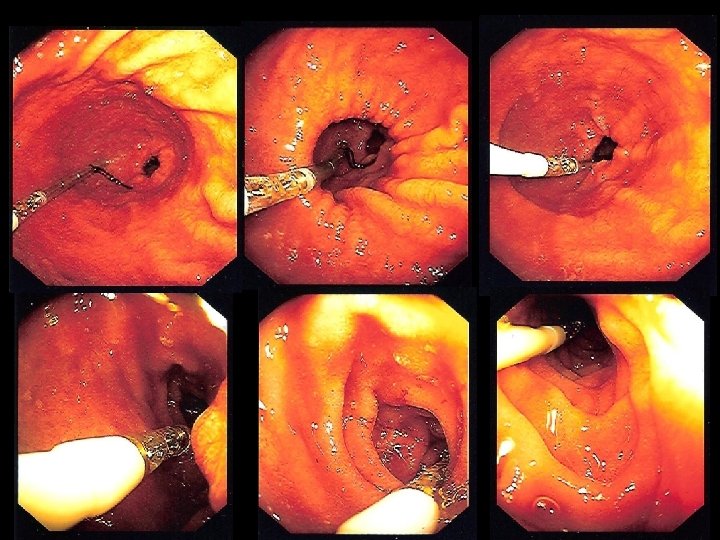

Post-pyloric feeding

Post-pyloric feeding

Post-pyloric feeding

Post-pyloric feeding